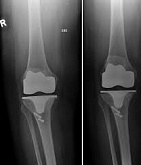

Endoprothetik des Kniegelenks

In den späten Stadien der Arthrose des Knies durch eine ausgeprägte Begrenzung der Bewegung begleitet, konstant starke Schmerzen, körperliche Unversehrtheit Verformung bis zur Genesung der einzige Weg ist der Ersatz des betroffenen Gelenks für eine künstliche - Endoprothetik.

Diese Methode ermöglicht es Ihnen, die richtige Form des Gliedes, eine vollständige Palette von Bewegung im Gelenke, zu entlasten ständige Schmerzen und Knirschen bei Bewegung und als Ergebnis wieder herzustellen, signifikant dem Patienten Lebensqualität zu verbessern.

Im Folgenden sind Röntgenaufnahmen und Fotografien, die die Strecke der Bewegung in der betroffenen Gelenke vor und nach der Operation veranschaulichen.